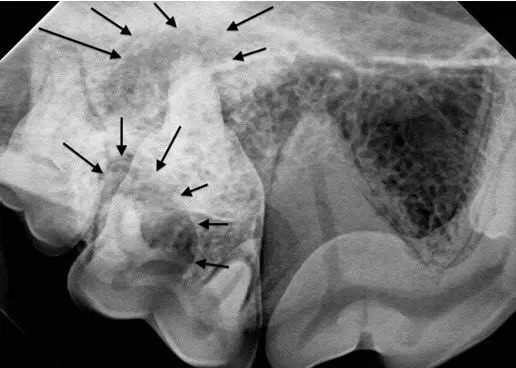

Large periapical lucencies are seen around the palatal (upper group of arrows) and distal (lower group of arrows) roots of 109. The large distal root of 108 appears to be normal in this view. Views showing the mesio-buccal and palatal roots of 108 were also normal. The PAL surrounding the distal root of 109 likely extends to the mesial root of 110.

The large periapical lucencies show that 109, not 108 is the source of the problem. One additional technique that might have been utilized would be to place a short size 20 to 30 gutta percha point into the draining tract. Gutta percha points are inexpensive, flexible and radio-opaque, and can help clarify the source of the drainage. Most human dentists have gutta percha in their practices, and would likely give you a few points to have on hand. Sizes 20, 25 or 30 would all be suitable for this purpose.

109 should either be extracted or treated with root canal therapy. If 109 is extracted, extraction of 110 should also be considered since the apical pathology visible on the distal root of 109 is so closely associated with the apex of the mesial root of 110. If 109 is treated with root canal therapy, 110 should be closely monitored for development of periapical pathology indicative of endodontic disease.